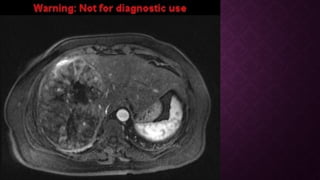

RESONANCIA MAGNETICARESONANCIA MAGNETICA

• T1

• variable

• iso- o hiperintensa del hígado circundante

• hiperintensidad puede deberse a

• grasa intratumoral

• disminución de la intensidad en el hígado

• T1 C + (Gd)

• mejora es generalmente arterial ("hypervascularity")

• "lavado rápido", convirtiéndose en hipointenso para el resto del hígado (96% específico) (esto

se debe a que el suministro a los CHC es predominantemente de la arteria hepática en lugar

de la vena porta)

• la mejora del borde puede persistir (denominada cápsula)

• se ha desarrollado un sistema de clasificación por imágenes ( LI-RADS ) para estratificar

lesiones

RESONANCIA MAGNETICARESONANCIA MAGNETICA •T1 • variable • iso- o hiperintensa del hígado circundante • hiperintensidad puede deberse a • grasa intratumoral  • disminución de la intensidad en el hígado • T1 C + (Gd) • mejora es generalmente arterial ("hypervascularity") • "lavado rápido", convirtiéndose en hipointenso para el resto del hígado (96% específico) (esto se debe a que el suministro a los CHC es predominantemente de la arteria hepática en lugar de la vena porta) • la mejora del borde puede persistir (denominada cápsula) • se ha desarrollado un sistema de clasificación por imágenes ( LI-RADS ) para estratificar lesiones